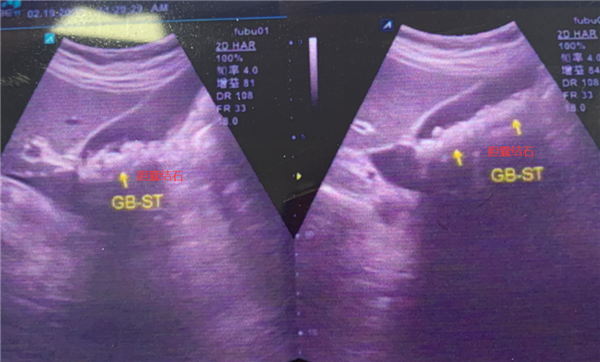

京都醫(yī)院檢查提示,涂婆婆膽囊里有近300顆結(jié)石,最大的有1公分左右。如果繼續(xù)放任不管,結(jié)石將會(huì)在涂婆婆膽囊內(nèi)越長(zhǎng)越多

并持續(xù)刺激膽囊黏膜,不僅膽囊會(huì)被結(jié)石撐大失去功能,甚至還會(huì)導(dǎo)致膽囊化膿穿孔,引起嚴(yán)重的急性腹膜炎等。

經(jīng)過(guò)一個(gè)多小時(shí)的手術(shù),成功經(jīng)患者肚臍眼位置取出297顆金黃色的小結(jié)石,乍眼看去就像一顆顆“玉米粒”似的,最重要的是,膽囊由于功能完好也被順利保住了!